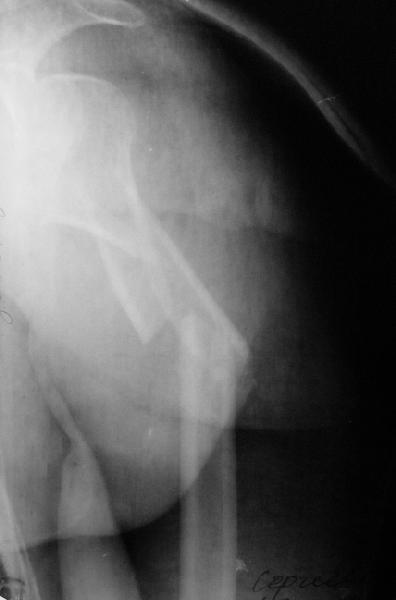

Дорогие коллеги,Мужчина 44 л. упал с крыши дачи 6 августа. Картинки в приложении. Лет 5 назад нде-то оперирован по поводу привычного вывихв этого же плеча.После операции не вывихивал до этой травмы.Как тут лечить? Есть ли шансы на закрытое вправление? Чем лучше фиксировать? Какие меры принять с учетом бывшего и нынешнего вывиха? Заранее спасибо. Dear colleagues, A male 44 y.o. admitted to our unit. Injured at Aug. 6 - fall from 3 m. Images attached. Five years ago was operated somewhere else for recurrent dislocation of thу same shoulder, no data what was done. What would be optimal treatment option? Any chance of closed reduction? What should be done to address the current and past dislocations? THX.

This is an anterior fracture/dislocation with shaft extension-no chance for closed reduction-probably contraindicated, especially since the injury is now 19 days old. We do these supine on a radiolucent table with an arm board extension-you now have an unobstructed radiographic view of the entire upper extremity both AP and lateral with excellent axillary views of the glenohumeral joint to assess your reduction and screw placement. This is the perfect indication for a locking plate via the traditional deltopectoral approach. Use the biceps tendon to stay anatomically oriented during the approach and be sure to check the rotation post plate application. In general, we have not performed any soft tissue stabilization procedures during the fixation, may stay away from external rotation past neutral during rehab and early motion protocol. This one should do fine.

Попытка закрыто изменить положение не удалась. Передним доступом сделали открытую репозицию, гленоид без особенностей. Временно фиксировали спицами и остроконечным костедержателем. Фиксировали гвоздем T2 PHN (Stryker). Для профилактики вывихов после введения проксимальных винтов ротировали дистальный отдел кнаружи на 30

градусов как аналог остеотомии по Weber. Снимки в приложении. Комментарии и критика привествуются.

Attempt of closed reduction failed. Open reduction via anterior approach. The head was temporarily fixed by wires and sharp clamps. Fixation by a nail - T2 PHN (Stryker). The distal fragment has been rotated 30 degrees externally after proximal locking for dislocation prevention as "virtual" Weber osteotomy. Images attached.